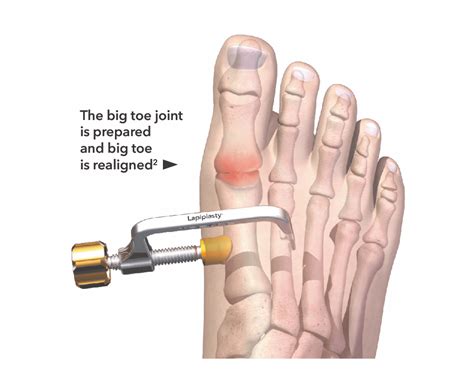

The journey to recovery or maintenance depends largely on the severity of the underlying condition. For many, conservative treatments such as physical therapy, lifestyle adjustments, and medication are sufficient to lead a pain-free life. In more advanced cases where structural damage has occurred, surgical options may be discussed. Modern surgical techniques for the big toe joint are highly sophisticated, often focusing on joint preservation rather than simple fusion, which helps maintain natural movement patterns.